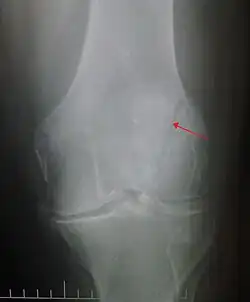

Patella fracture

A patella fracture is a break of the kneecap.[1] Symptoms include pain, swelling, and bruising to the front of the knee.[1] A person may also be unable to walk.[1] Complications may include injury to the tibia, femur, or knee ligaments.[2]

It typically results from a hard blow to the front of the knee or falling on the knee.[1]The patella can also be fractured indirectly. For example, a sudden contraction of the quadriceps muscle in the knee can pull apart the patella.[1]Diagnosis is based on symptoms and confirmed with X-rays.[3] In children an MRI may be required.[3]

Diagnosis is based on symptoms and confirmed with X-rays.[3] In children an MRI may be required.[3]

The patella can break in various ways depending on the way it is injured, and into two or more pieces.[1] Types include transverse, the most common, with one fracture line;[5] marginal; osteochondral; and the rare vertical type, or stellate, where a direct compression force gives rise to a comminuted pattern.[5][7] Patella fractures can be further classified as displaced, where the broken ends of bone do not line up correctly and separate by more than 2mm, or undisplaced and stable where pieces of bone remain in contact with each other.[1][7] If fragments of patella bone stick out from the skin it is known as an open patella fracture, and closed if the overlying skin is intact.[1]